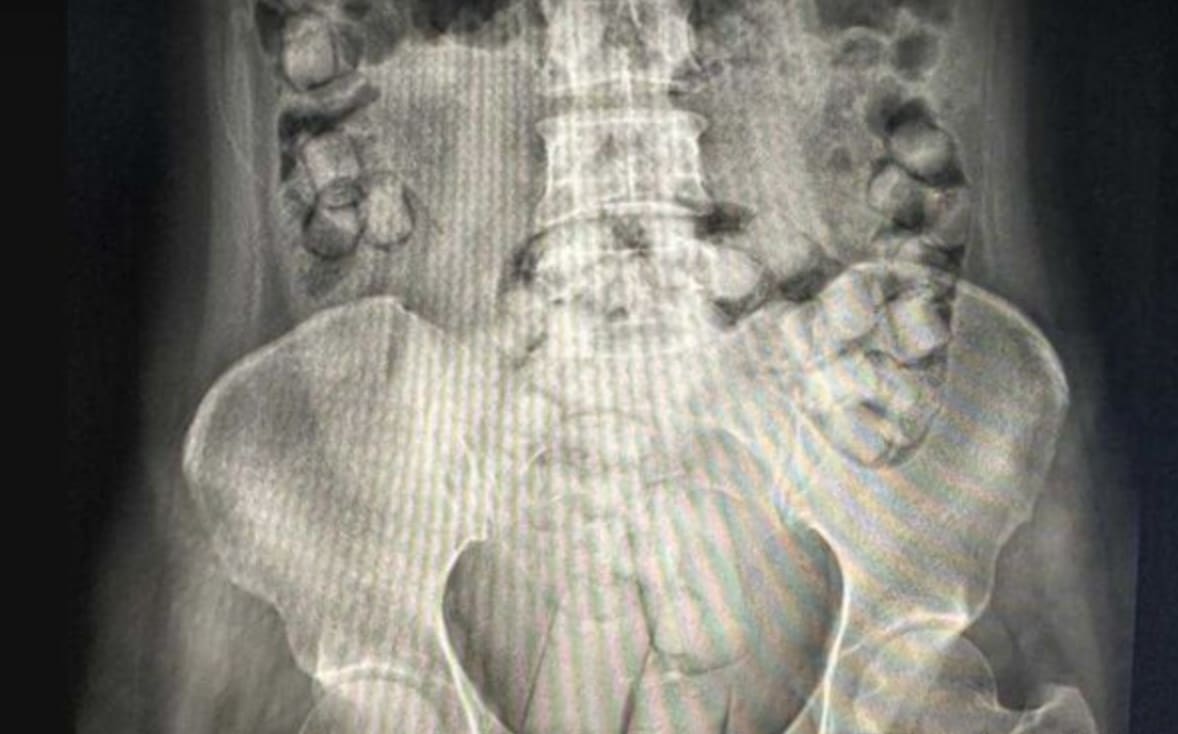

两人入境时,因神情异常,被带往医院进行X光检查,医护人员发现体内布满异物阴影,随即安排灌肠及服用泻药协助排出。

X光显示女子体内藏有毒品。(图:ETtoday新闻云)